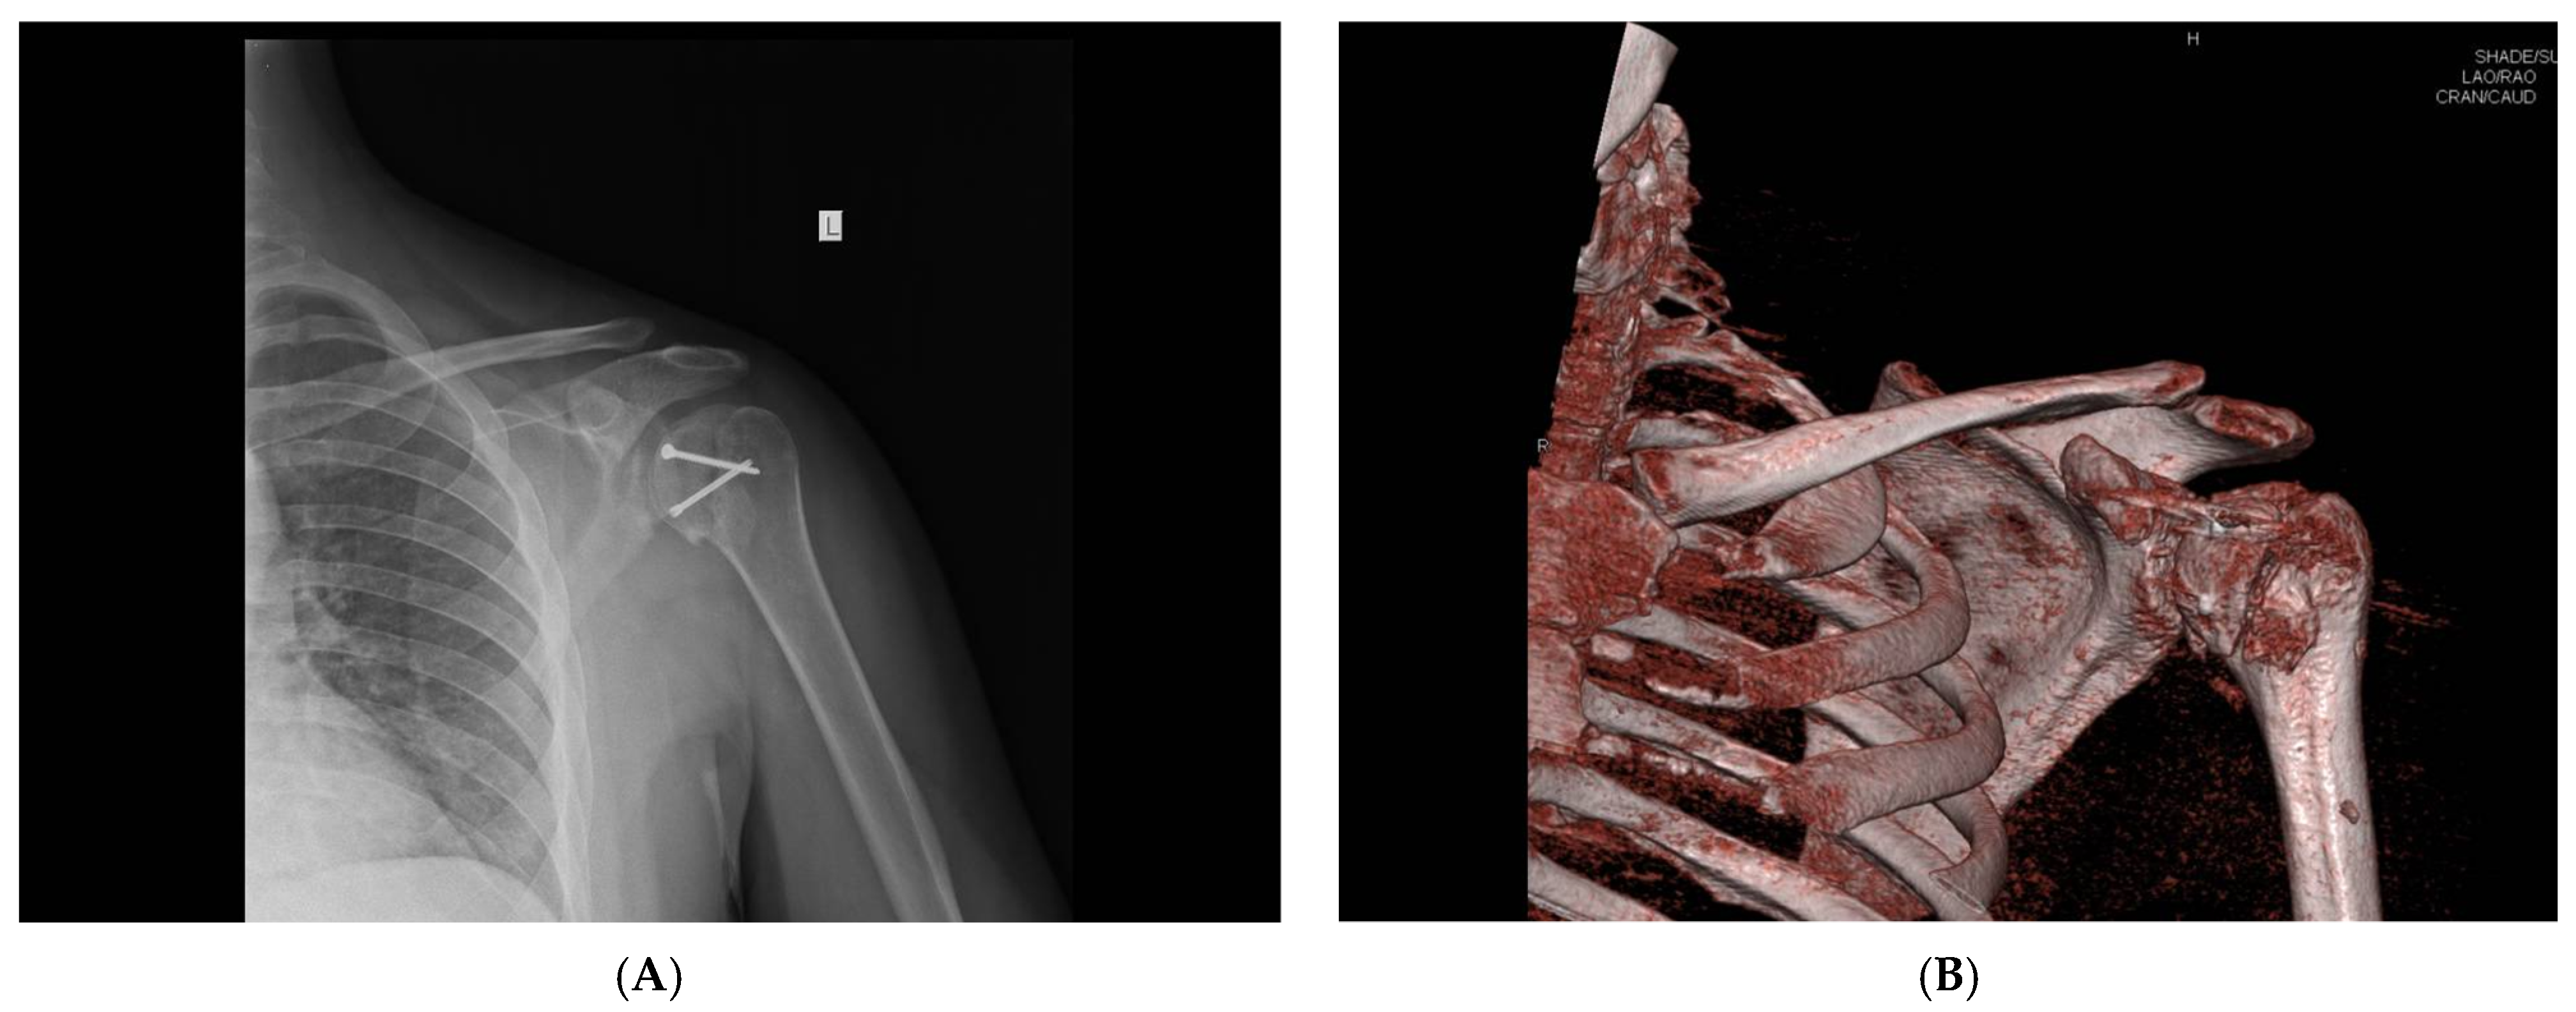

All femoral condyle osteochondral allografts were fresh-frozen and stored at −80 °C. They were tested for bacterial contamination, as well as serologically for hepatitis (A, B and C) and human immunodeficiency virus. On the day of surgery, the osteochondral grafts were thawed and submerged in 300 mL of saline solution with five ampoules of 120 mg gentamycin. Before placement, the grafts were washed with 500 mL of pure physiological solution. An oscillating saw was used to prepare the humeral head defect site for the osteochondral allograft. The dimensions of the lesion were carefully measured, and a similarly sized allograft was modeled accordingly (Figure 2 and Figure 3). Tenodesis of the long head of the bicep tendon was performed in all patients. Fixation of the allograft to the humeral head was achieved using two cancellous screws in four patients, while two Herbert screws [8] were used in the remaining sixteen patients, all placed subchondrally (Figure 4). After the shoulder joint was reduced into place, the reinsertion of the m. subscapularis was performed in its anatomical position (because osteotomy of the lesser tubercle was performed during the procedure). During the immobilization period, the m. subscapularis healed in its anatomical position. The shoulder joint capsule was sutured with absorbable sutures and the wound was closed in layers.

Figure 2. Intraoperative presentation of a reverse Hill–Sachs lesion (photo from the personal archive of intraoperative photos of the author).